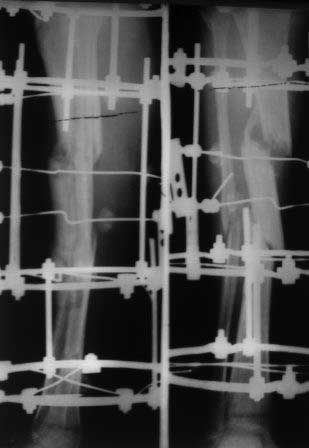

Здравствуйте, уважаемые коллеги!Больной 1976г.р. получил тяжелую сочетанную травму в апреле ,был в коме около 1 месяца. 09.05.12г.операция КДО аппаратом Илизарова в другом регионе,перелом шейки бедра пропущен. Обратился к нам сегодня для дальнейшего лечения, ходит c двумя костылями, укорочение 4см, на правой голени аппарат Илизарова в вальгусном положении, разболтанность в пр.т/б суставе,повреждение ипсилатеральное. В плане сначала БИОС б/берцовой кости после остеотомии м/берцовой и коррекции деформаций голени,после т/эндопротезирование пр. т/б сустава, Нужен совет: 1.последовательность операции? 2.или другие варианты лечения? С уважением Абдурашид. р-снимки прилагаются-от 17.12.12г.

Если нет признаков воспаления (раны, воспаление м/тканей вокруг спиц и т.п.) или остеомиелита голени, то я бы начал с протезирования сустава, создав опорную конечность, а затем доводка голени до оптимальной биомеханических взаимоотношений с другой конечностью при ходьбе для расставания с костылями. Кстати второй этап можно оставить проводить в аппарате, с его естественно коррекцией по классике Илизарова, или аппарат на штифте ( как вариант). Обязательно учесть последствия комы. Если же есть воспаление на голени фиксированной аппаратом, то начинать с голени и корректировать воспалительную реакцию. С уважением Ангельский Александр.

Учитывая исходную картинку - результат неплохой. Однако! 1.Стержень торчит в коленку. 2.Вальгус все же есть, о величине судить не берусь. 3.Укорочение осталось, судя по м/берцовой кости. Колено явно пострадает.

Как стопа? Сколько укорочение и что собираетесь с ним делать?

-".Вальгус все же есть, о величине судить не берусь"-По сравнение с тем что было до операции, я думаю рентгенологически градусов 2-3 допустимо, тем более клинически это не заметно.

-".Укорочение осталось"-да,укорочение в пределах 1,5-2см за счет голени и еще 4см за счет шейки бедра и для устранения этого опять на месяцы аппарат( он находился на аппарате около 8 месяцев)